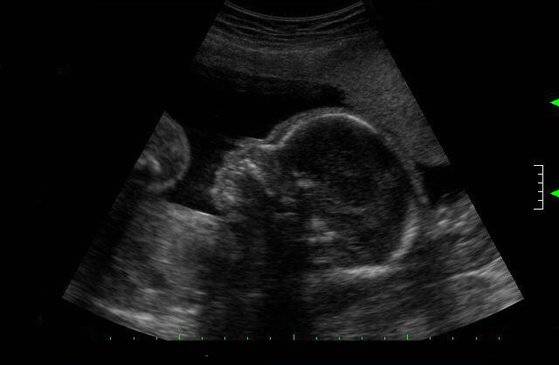

태아 초음파 사진 [중앙포토]